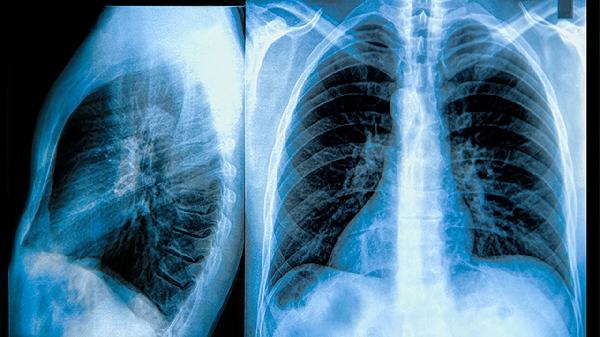

肺部肿瘤5.7厘米属于较大体积,通常需要进一步评估其性质及分期以判断严重程度。肺部肿瘤的严重性主要取决于肿瘤性质、是否转移、患者基础健康状况等因素。

良性肺部肿瘤生长缓慢,边界清晰,多数情况下通过手术切除可治愈,对周围组织压迫症状较轻。若为恶性,5.7厘米的肿瘤可能已进入中晚期,存在局部浸润或远处转移风险,需结合病理类型、淋巴结状态等综合评估。恶性肿瘤可能伴随咳嗽、咯血、胸痛等症状,需通过穿刺活检或影像学明确性质。

部分特殊类型肿瘤如炎性假瘤或结核球可能表现为类似体积的占位,但生长特性与恶性肿瘤不同。此类情况需结合病史、实验室检查及动态观察判断,部分可通过抗感染或抗结核治疗缩小病灶。若肿瘤压迫气管或神经,可能引起呼吸困难、声音嘶哑等急症,需紧急干预。